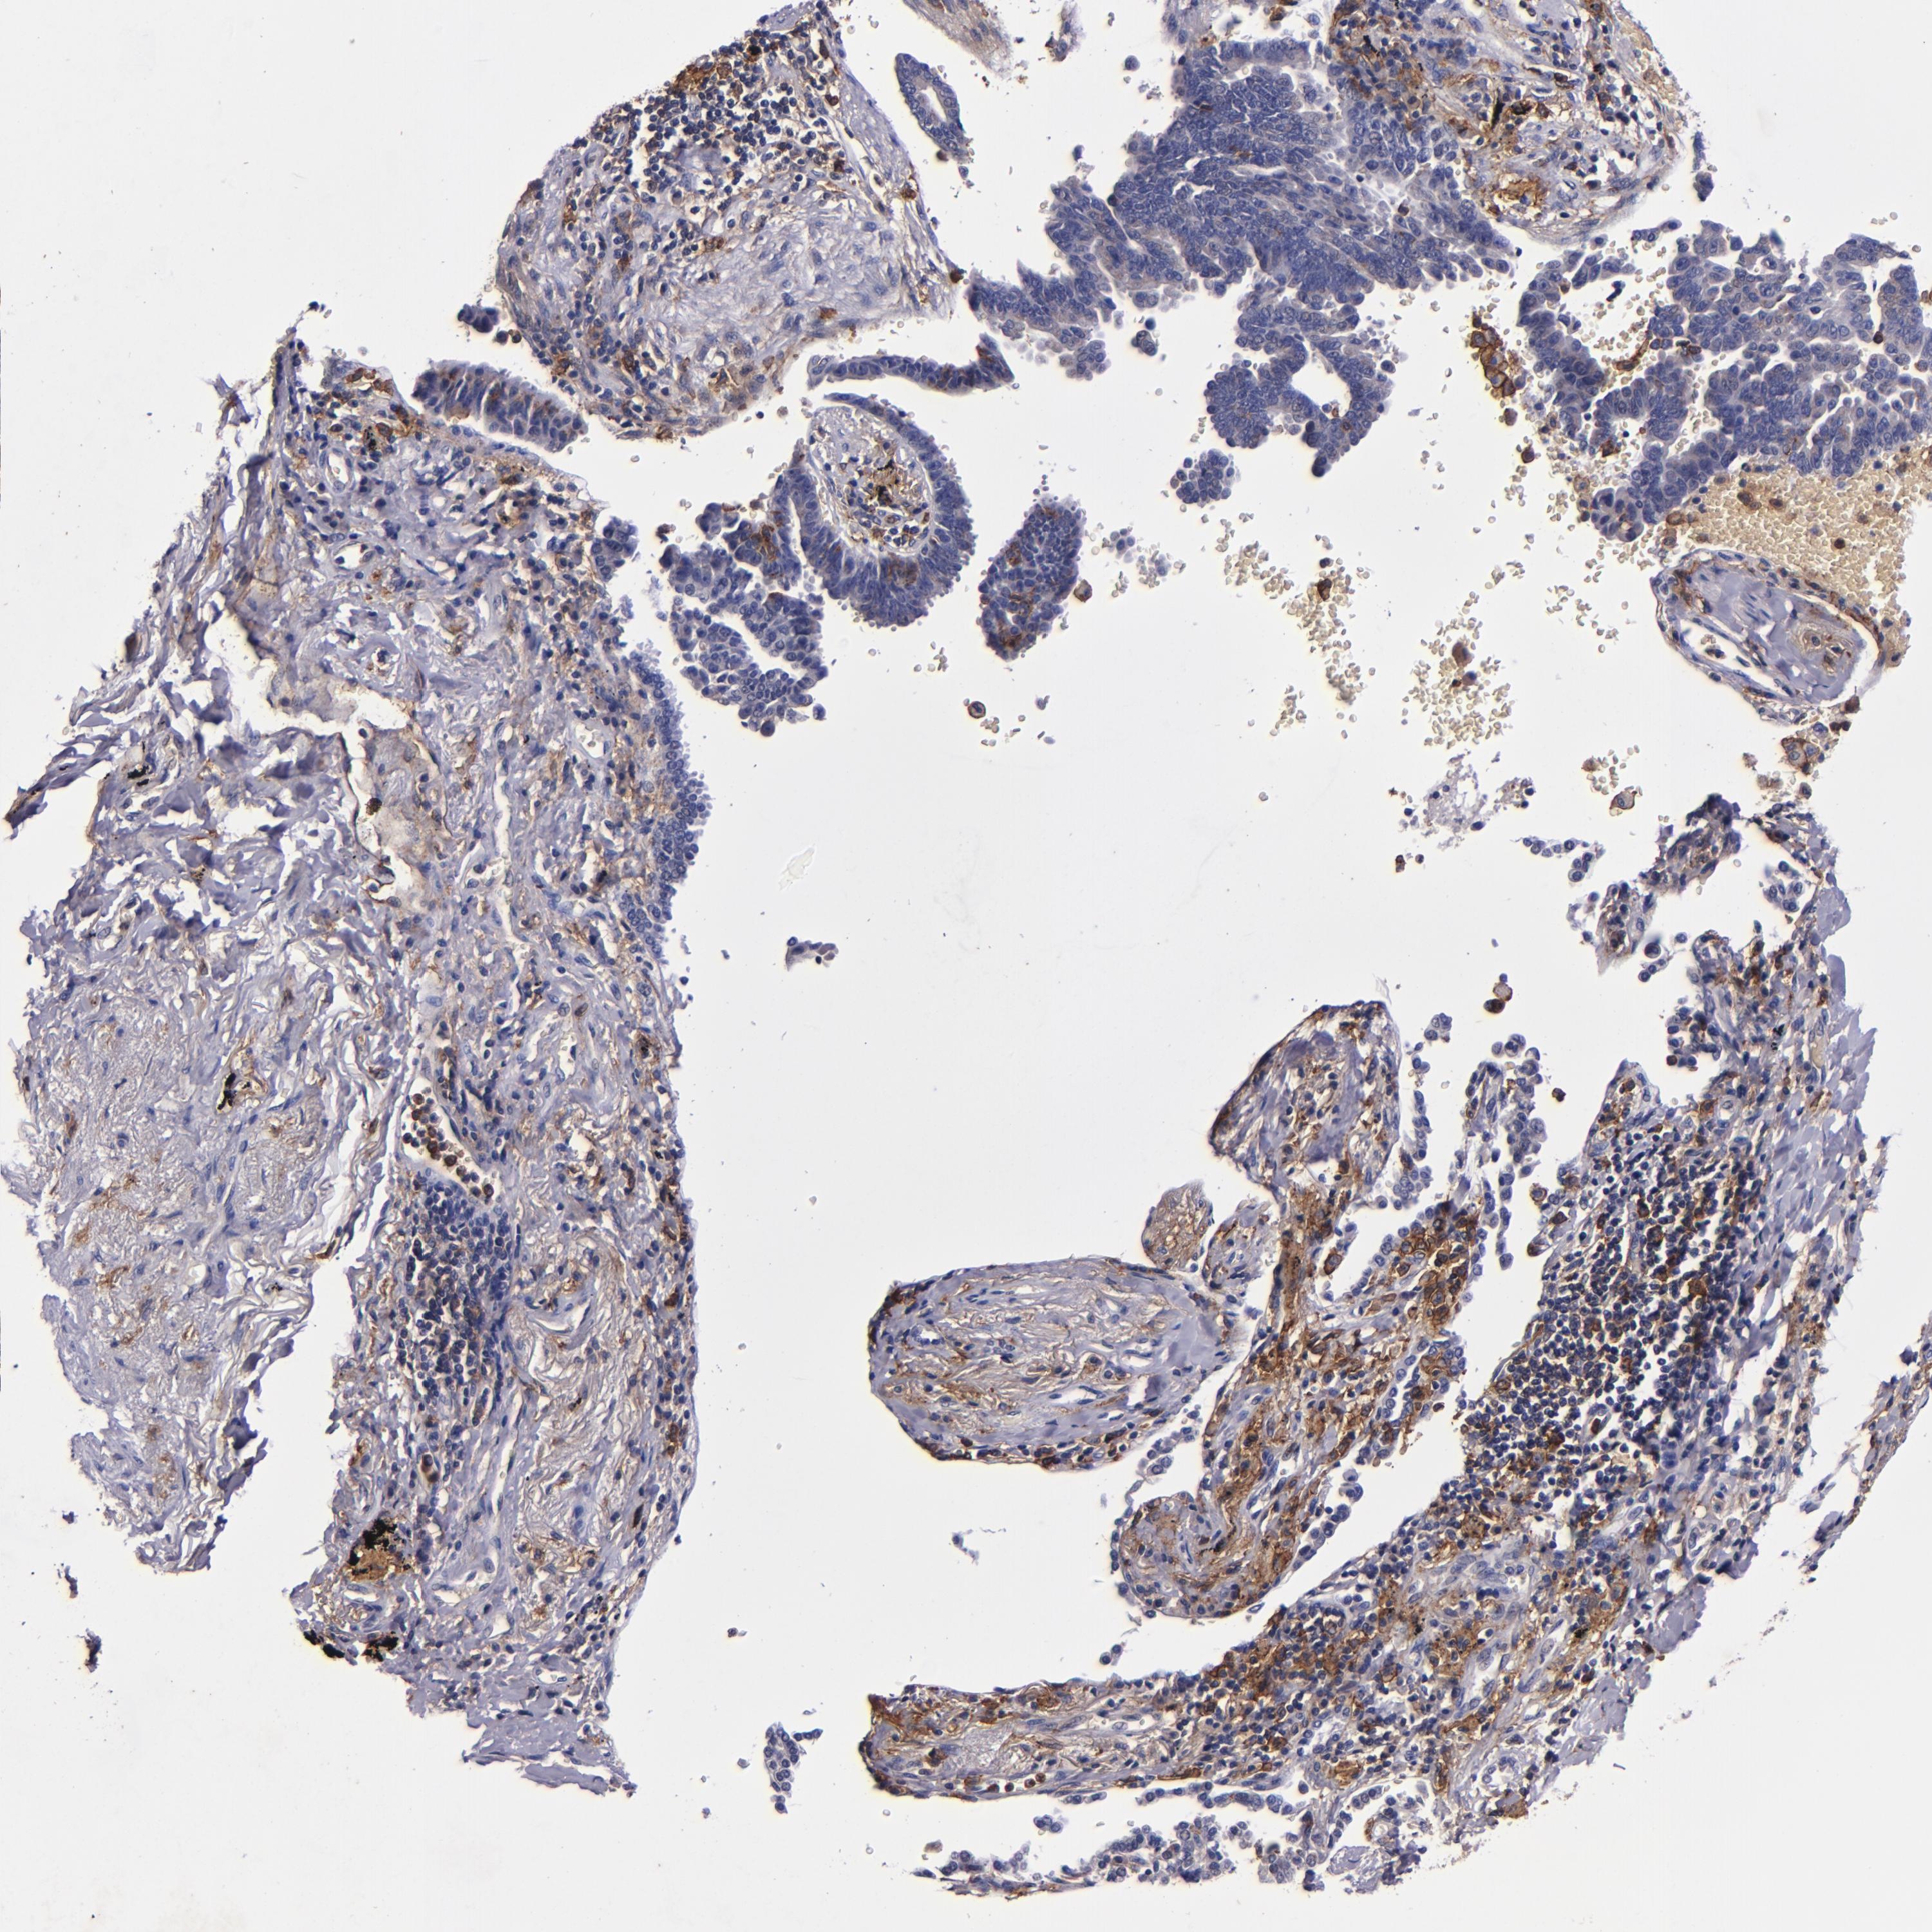

LUNG SQUAMOUS CELL CARCINOMA (TCGA) - Interactive survival scatter ploti

The Survival Scatter plot shows the clinical status (i.e. dead or alive) for all individuals in the patient cohort, based on the same data that underlies the corresponding Kaplan-Meier plots. Patients that are alive at last time for follow-up are shown in blue and patients who have died during the study are shown in red.

The x-axis shows the expression levels (FPKM) of the investigated gene in the tumor tissue at the time of diagnosis. The y-axis shows the follow-up time after diagnosis (years). Both axes are complimented with kernel density curves demonstrating the data density over the axes. The top density plot shows the expression levels (FPKM) distribution among dead (red) and alive patients (blue). The right density plot shows the data density of the survived years of dead patients with high and low expression levels respectively, stratified using the cutoff indicated by the vertical dashed line through the Survival Scatter plot. This cutoff is automatically defined based on the FPKM cutoff that minimizes the p-score. The cutoff can be changed by dragging the vertical line or by entering a cutoff value in the square labeled "Current cut-off".

Under the Survival Scatter plot the p-score landscape (black curve; left axis) is shown together with dead median separation (red curve; right axis). Dead median separation is the difference in median mRNA expression between patients who have died with high and low expression, respectively. It is calculated as follows: median FPKM expression of dead patients with high expression - median FPKM expression of dead patients with low expression. This is intended to aid the user in visually exploring custom cutoffs and the associated p-scores and dead median separation.

Individual patient data is displayed and can be filtered by clicking on one or more of the category buttons on the top of the page. Categories describing expression level and patient information include: high, low, alive, dead, female, male and tumor stages. The scale of the x-axis can be toggled between linear and log-scale by clicking on the "x log" button. Mouse-over function shows TCGA ID, patient information and mRNA expression (FPKM) for each patient.

& Survival analysisi

Kaplan-Meier plots summarize results from analysis of correlation between mRNA expression level and patient survival. Patients were divided based on level of expression into one of the two groups "low" (under cut off) or "high" (over cut off). X-axis shows time for survival (years) and y-axis shows the probability of survival, where 1.0 corresponds to 100 percent.

SIRPA is potential prognostic, high expression is unfavorable in Lung Squamous Cell Carcinoma (TCGA)

Best expression cut offi

Based on the FPKM value of each gene, patients were classified into two groups and association between prognosis (survival) and gene expression (FPKM) was examined. The best expression cut-off refers the FPKM value that yields maximal difference with regard to survival between the two groups at the lowest log-rank P-value. Best expression cut-off was selected based on survival analysis .

When clicking on this number, the vertical dashed line indicating cut-off, the interactive survival plot, and the Kaplan-Meier curve will be adjusted to show results based on the best expression cut-off.

: 33.8

P scorei

Log-rank P value for Kaplan-Meier plot showing results from analysis of correlation between mRNA expression level and patient survival.

N/A

TCGA RNA samplesi

RNA-seq data is reported as average FPKM (number Fragments Per Kilobase of exon per Million reads), generated by the The Cancer Genome Atlas (TCGA) .

Normal distribution across the dataset is visualized with box plots, shown as median and 25th and 75th percentiles. Points are displayed as outliers if they are above or below 1.5 times the interquartile range. FPKM values of the individual samples are presented next to the box plot.

Average pTPM 29.4

Number of samples 489